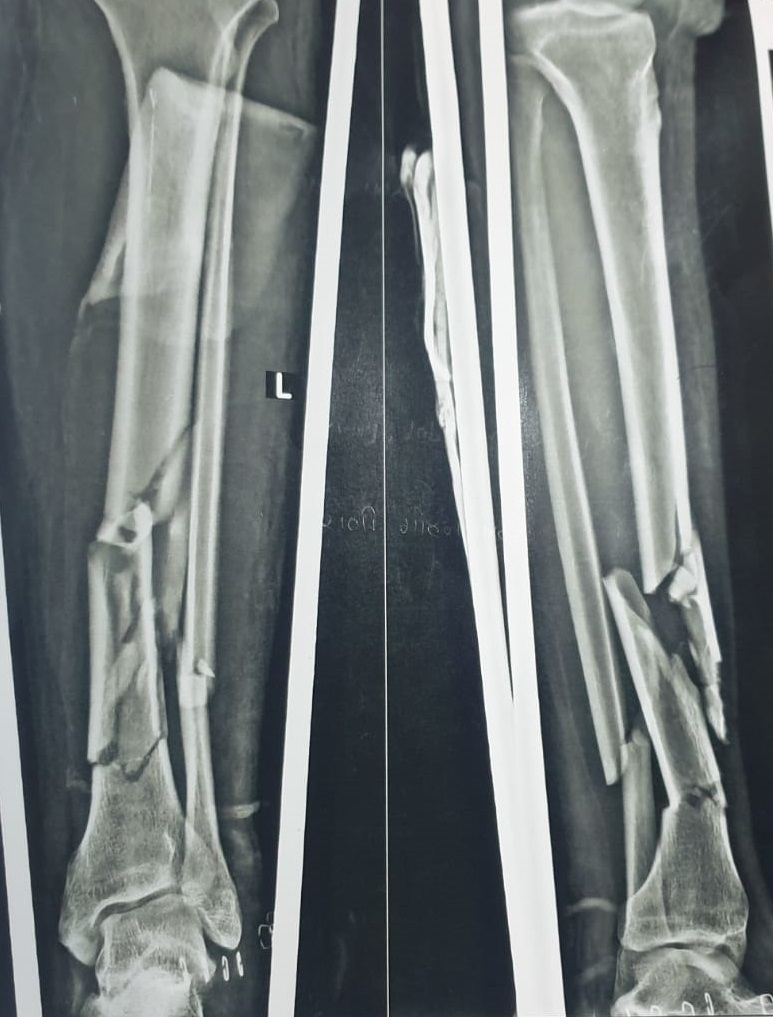

Preoperative Findings:

Radiological evaluation revealed multiple fracture segments in the midshaft region with loss of structural continuity. The Samay Surgical Pvt. Ltd.’s Expert Tibia Nail was chosen for its high mechanical strength and ability to support complex shaft injuries effectively.